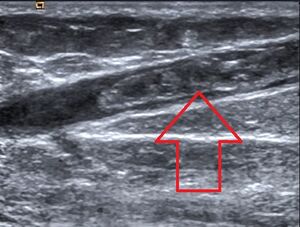

ولتخفيف أعراض انقطاع الحيض، تكون هناك حاجة في العادة لاستخدام علاج تعويض الهورمونات لسنوات قليلة فقط. وقد يكون العلاج مجازفة بالنسبة للنساء اللائي يعانين من أمراض معينة مثل سرطان الثدي، والجلطات الدموية، وأمراض الكبد. يجب أن يستمر العلاج بالهورمونات بغرض الوقاية من الأمراض لسنوات عديدة، أو ربما مدى الحياة. والعلماء غير متأكدين ما إذا كان العلاج طويل الأمد فعّالاً أو آمنًا. فقد أظهرت بعض الدراسات أن استخدام الهورمونات لفترات طويلة قد يزيد قليلاً من مخاطر إصابة المرأة بسرطان الثدي.

جلطات الدم